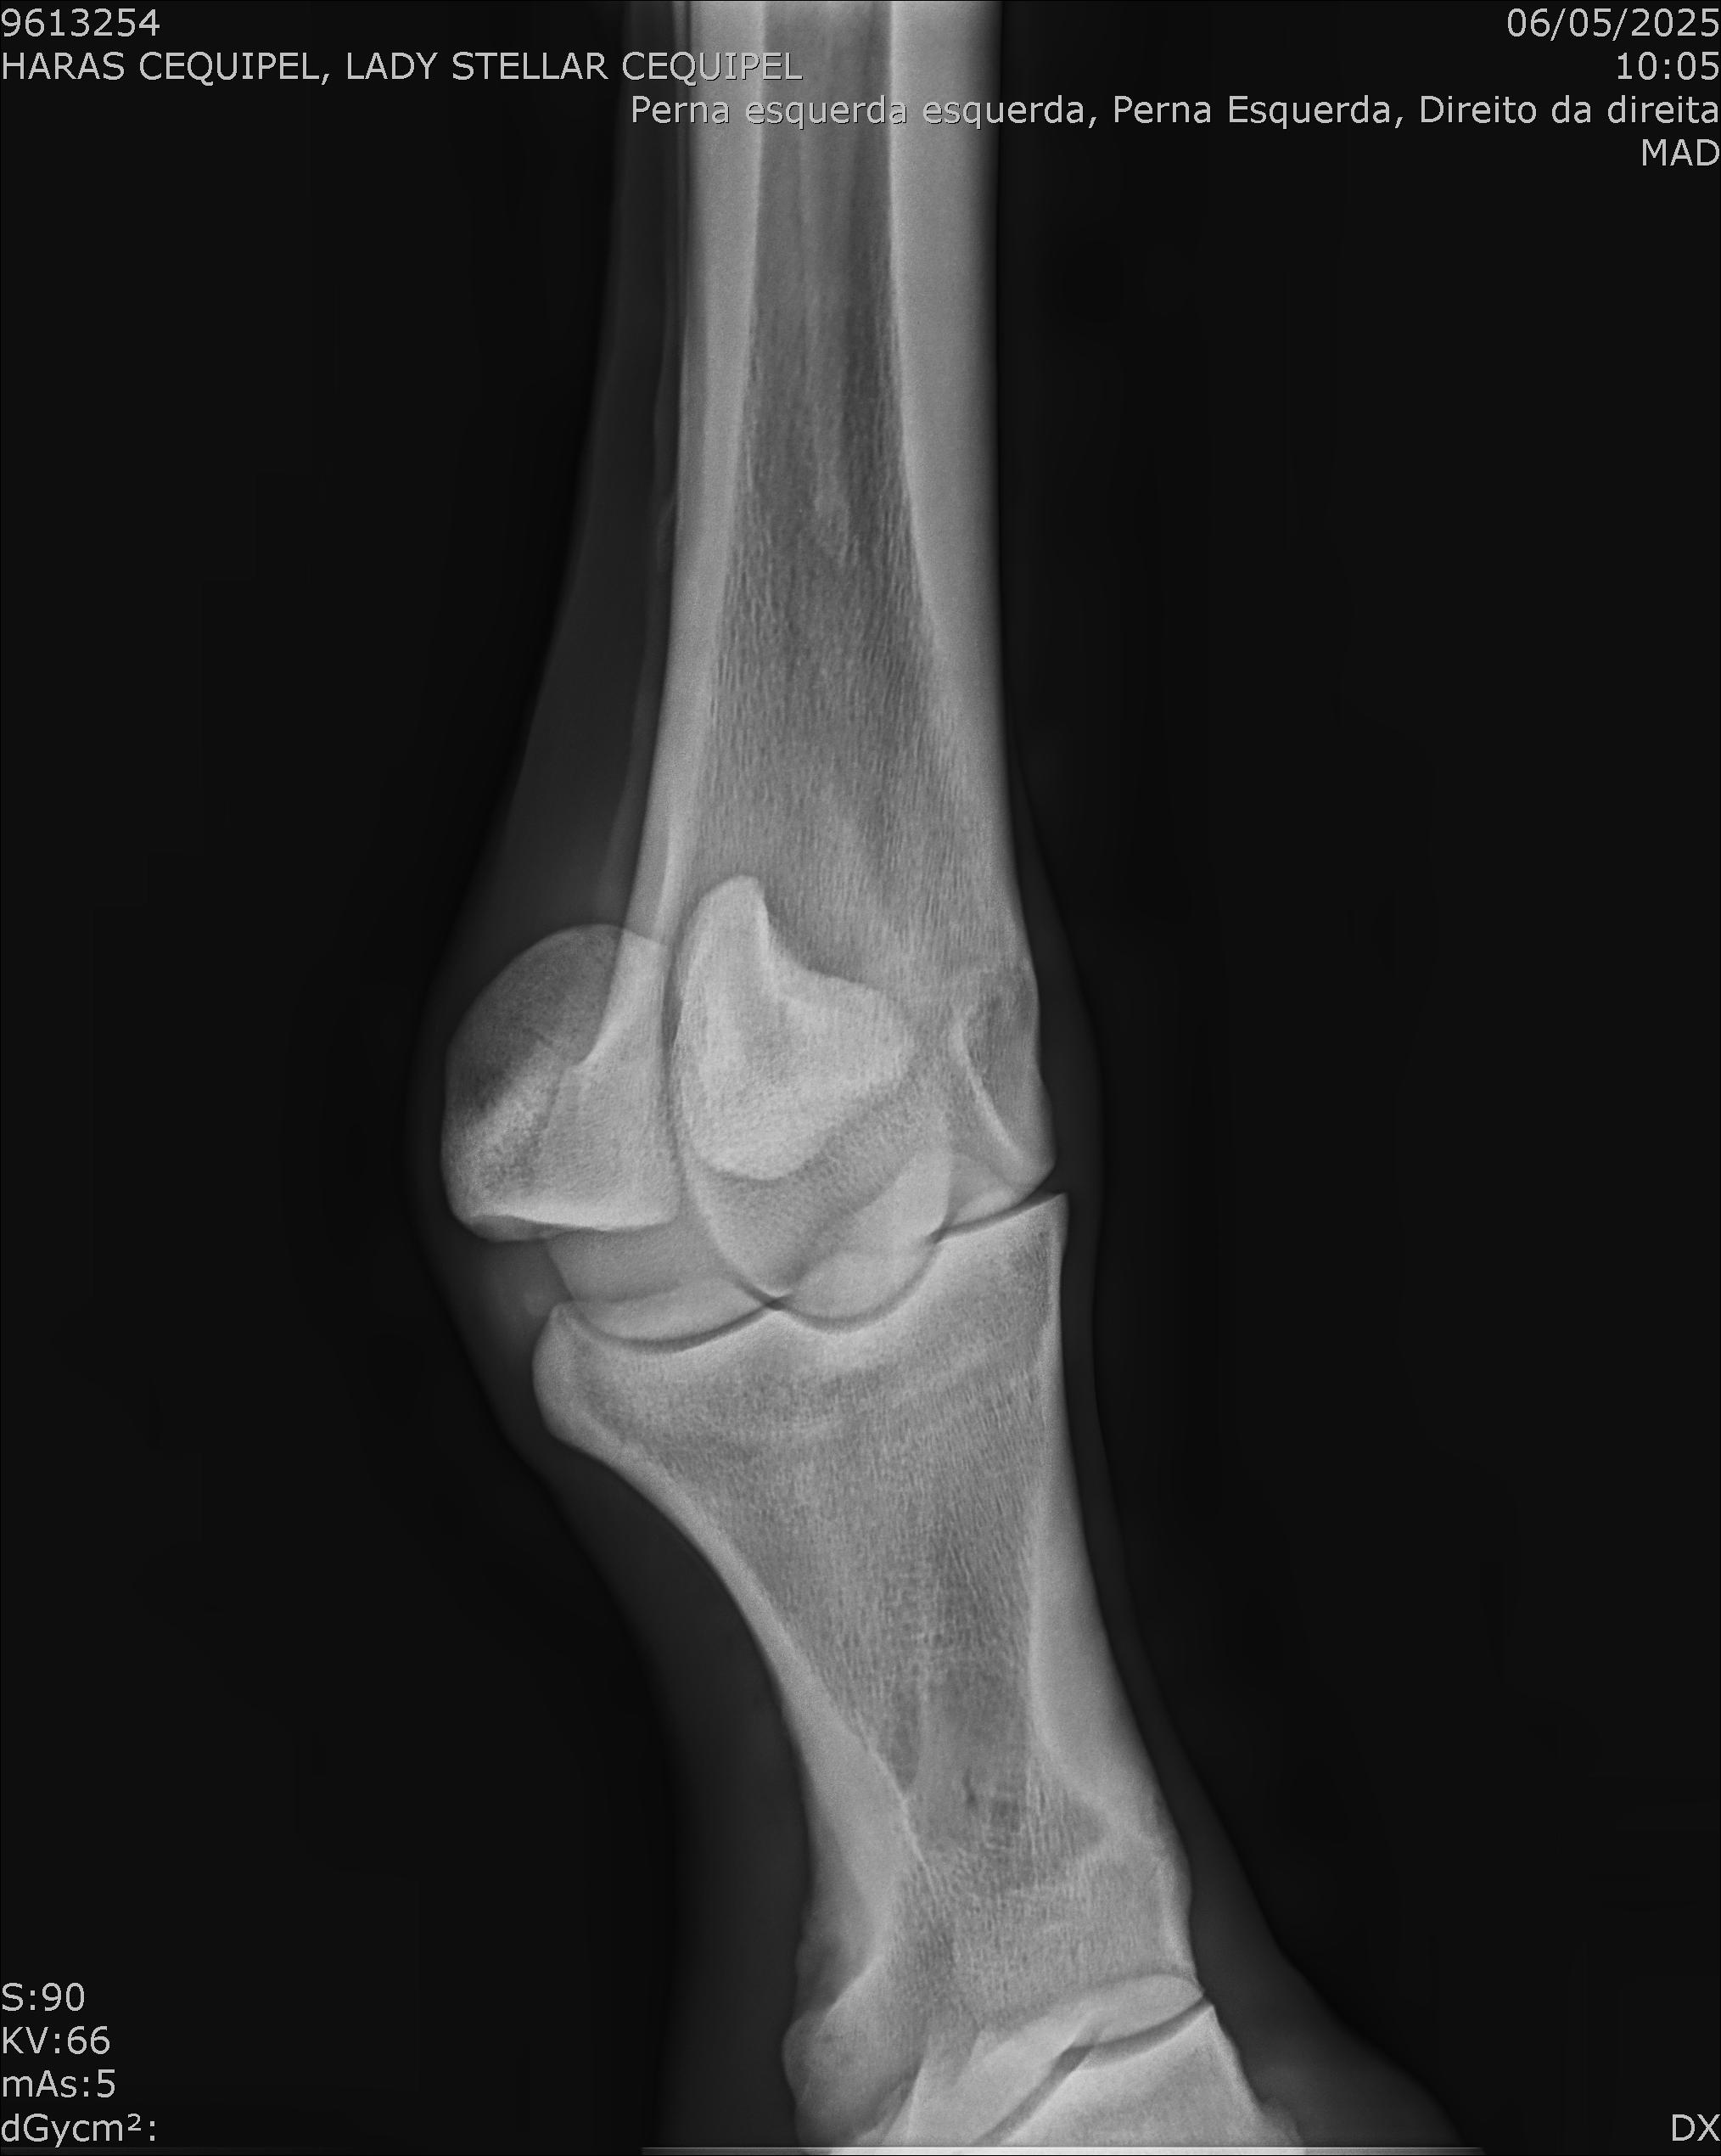

:: RAIOS-X DO LOTE